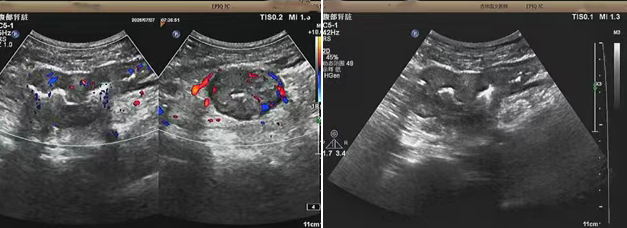

超聲檢查的結(jié)果進一步揭示了病情的細節(jié):下腹部偏左腸壁顯著增厚,原本清晰的層次結(jié)構(gòu)遭到破壞,周圍脂肪間隙變得模糊,網(wǎng)膜回聲也出現(xiàn)增強的現(xiàn)象,同時,腸腔狹窄的情況也得到了確認。經(jīng)過完善的檢查,最終將病變精準(zhǔn)定位在乙狀結(jié)腸 - 直腸交界區(qū),并且對病變范圍及周圍浸潤情況做出了評估,這些關(guān)鍵信息為后續(xù)的診療工作提供了重要依據(jù),讓醫(yī)生們能更有針對性地制定治療方案。

我院超聲檢查在此次診療過程中展現(xiàn)出了顯著的技術(shù)亮點。一方面,它能做到 “明察秋毫”,通過高頻探頭可以清晰地顯示腸壁各層結(jié)構(gòu)的變化,為臨床判斷病變性質(zhì)提供了客觀、準(zhǔn)確的依據(jù),讓醫(yī)生能更清晰地了解腸道內(nèi)部的病變狀態(tài)。另一方面,它實現(xiàn)了 “精準(zhǔn)評估”,不僅準(zhǔn)確找到了病變的位置,還能全面評估病變對周圍組織的影響,這對于協(xié)助醫(yī)生制定科學(xué)合理的治療方案起到了至關(guān)重要的作用,有助于提高治療的有效性和安全性。